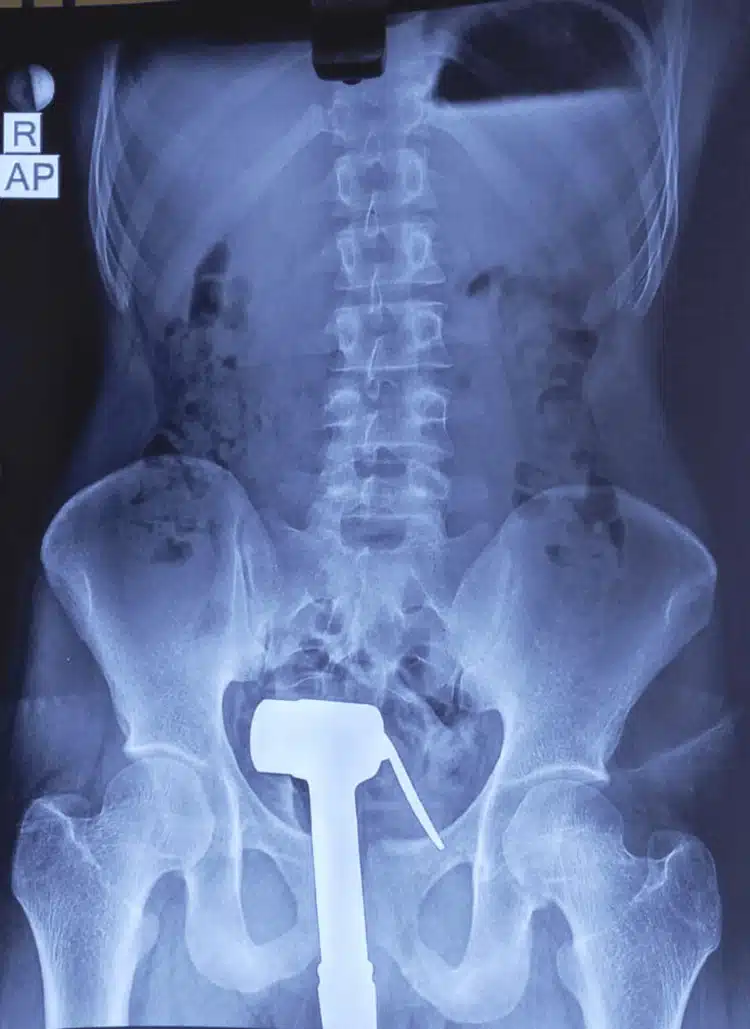

Sudah berulang kali mengeluarkannya sendiri namun gagal, tukang paip akhirnya terpaksa dipanggil untuk memotong besipaip berkenaan. Pemuda itu kemudiannya dikejarkan ke hospital untuk rawatan lanjut sebelum doktor menjalankan prosedur X-ray bagi mengesan kedudukan sebenar bidet yang sudah termasuk sehingga ke bahagian rektum (hujung usus besar).

Pernah buat benda sama 6 bulan sebelumnya, namun berjaya tarik sendiri

Setelah diberikan ubat bius, mujurlah bidet itu berjaya dikeluarkan dengan selamat meskipun terdapat kecederaan yang berlaku. Rupanya, pemuda itu merupakan orang kurang upaya (OKU) intelektual dan dia pernah melakukan perbuatan sama kira-kira 6 bulan sebelumnya. Namun ketika itu, dia berjaya mengeluarkannya sendiri.